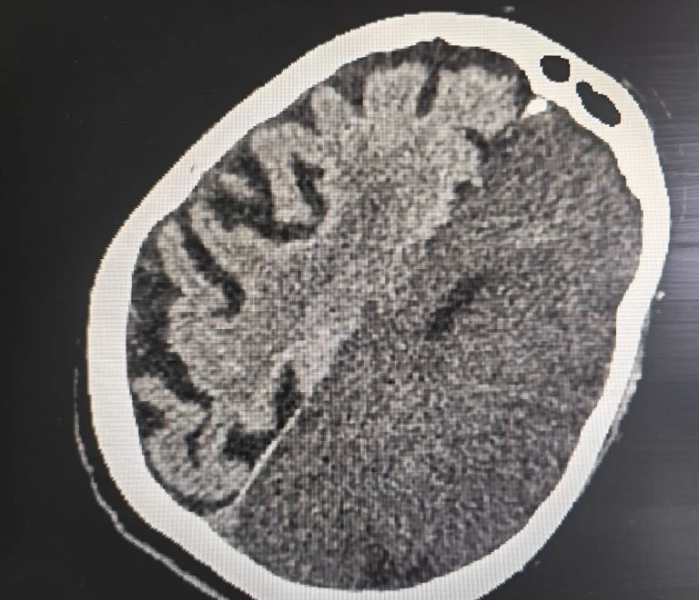

Срочно проведенная компьютерная томография подтвердила самые опасные опасения: у женщины диагностировали обширный ишемический инсульт. Это состояние означает, что из-за острого нарушения кровообращения значительный участок мозга перестал получать кислород, и клетки начали гибнуть. Подобный тип сосудистой катастрофы медики относят к числу наиболее тяжёлых: даже при своевременной помощи прогноз часто остаётся неблагоприятным, а риск летального исхода крайне высок.